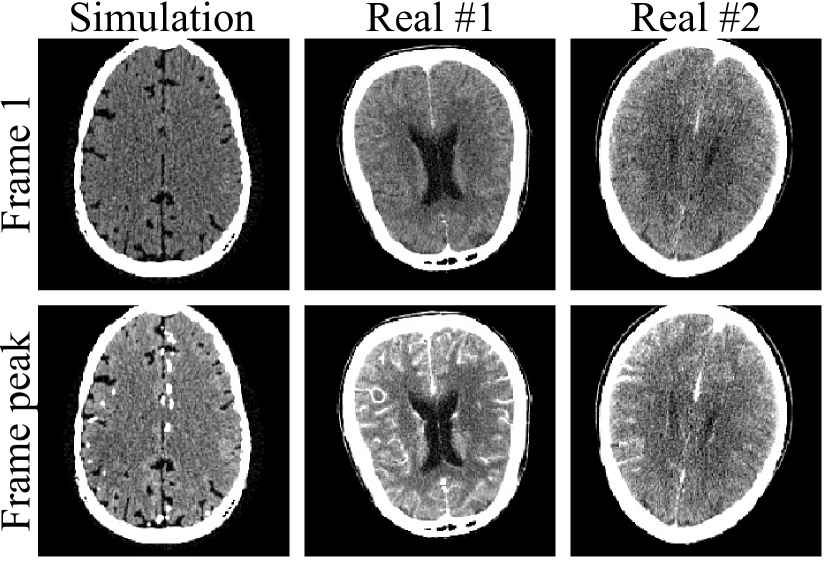

where p𝑝p is the forward projected value, and N0subscript𝑁0N_{0} is the assumed number of initial photons for the each ray. The CTP images were then reconstructed from noisy sinograms via filtered backprojection (FBP) with Hann filter. Distance-driven projector [49] was used for the forward projector and pixel-driven projector was used for the FBP. Three noise levels were simulated with N0=1×105,2×105,1×106subscript𝑁01superscript1052superscript1051superscript106N_{0}=1\times 10^{5},2\times 10^{5},1\times 10^{6}. 1×1051superscript1051\times 10^{5} and 2×1052superscript1052\times 10^{5} were chosen to match the noise levels of our real CTP images. 1×1061superscript1061\times 10^{6} was chosen for relatively low-noise images. Some of the training images are given in figure 2.

Refer to caption

Figure 2: Part of the training and testing dataset. The simulation images were under noise level of N0=2×105subscript𝑁02superscript105N_{0}=2\times 10^{5}. The first row showed the first frame, the second showed the frame at the peak of the time-concentration curve. The display windows are 40±80plus-or-minus408040\pm 80 HU.

V-A2 Real Data

We used the CTP images from the 2018 ISLES challenge dataset for real data validation [45, 46]. 20 patients with similar noise appearance were used, where 16 were used for training and 4 used for testing. Each patient had 2, 4, or 8 slices with 40 to 50 frames. All the patients were within 8 hours of symptom onset and a DWI was done for each patient within 3 hours of CTP. Infarct cores derived from the DWI images were also provided. Some of the real data are illustrated in figure 2.